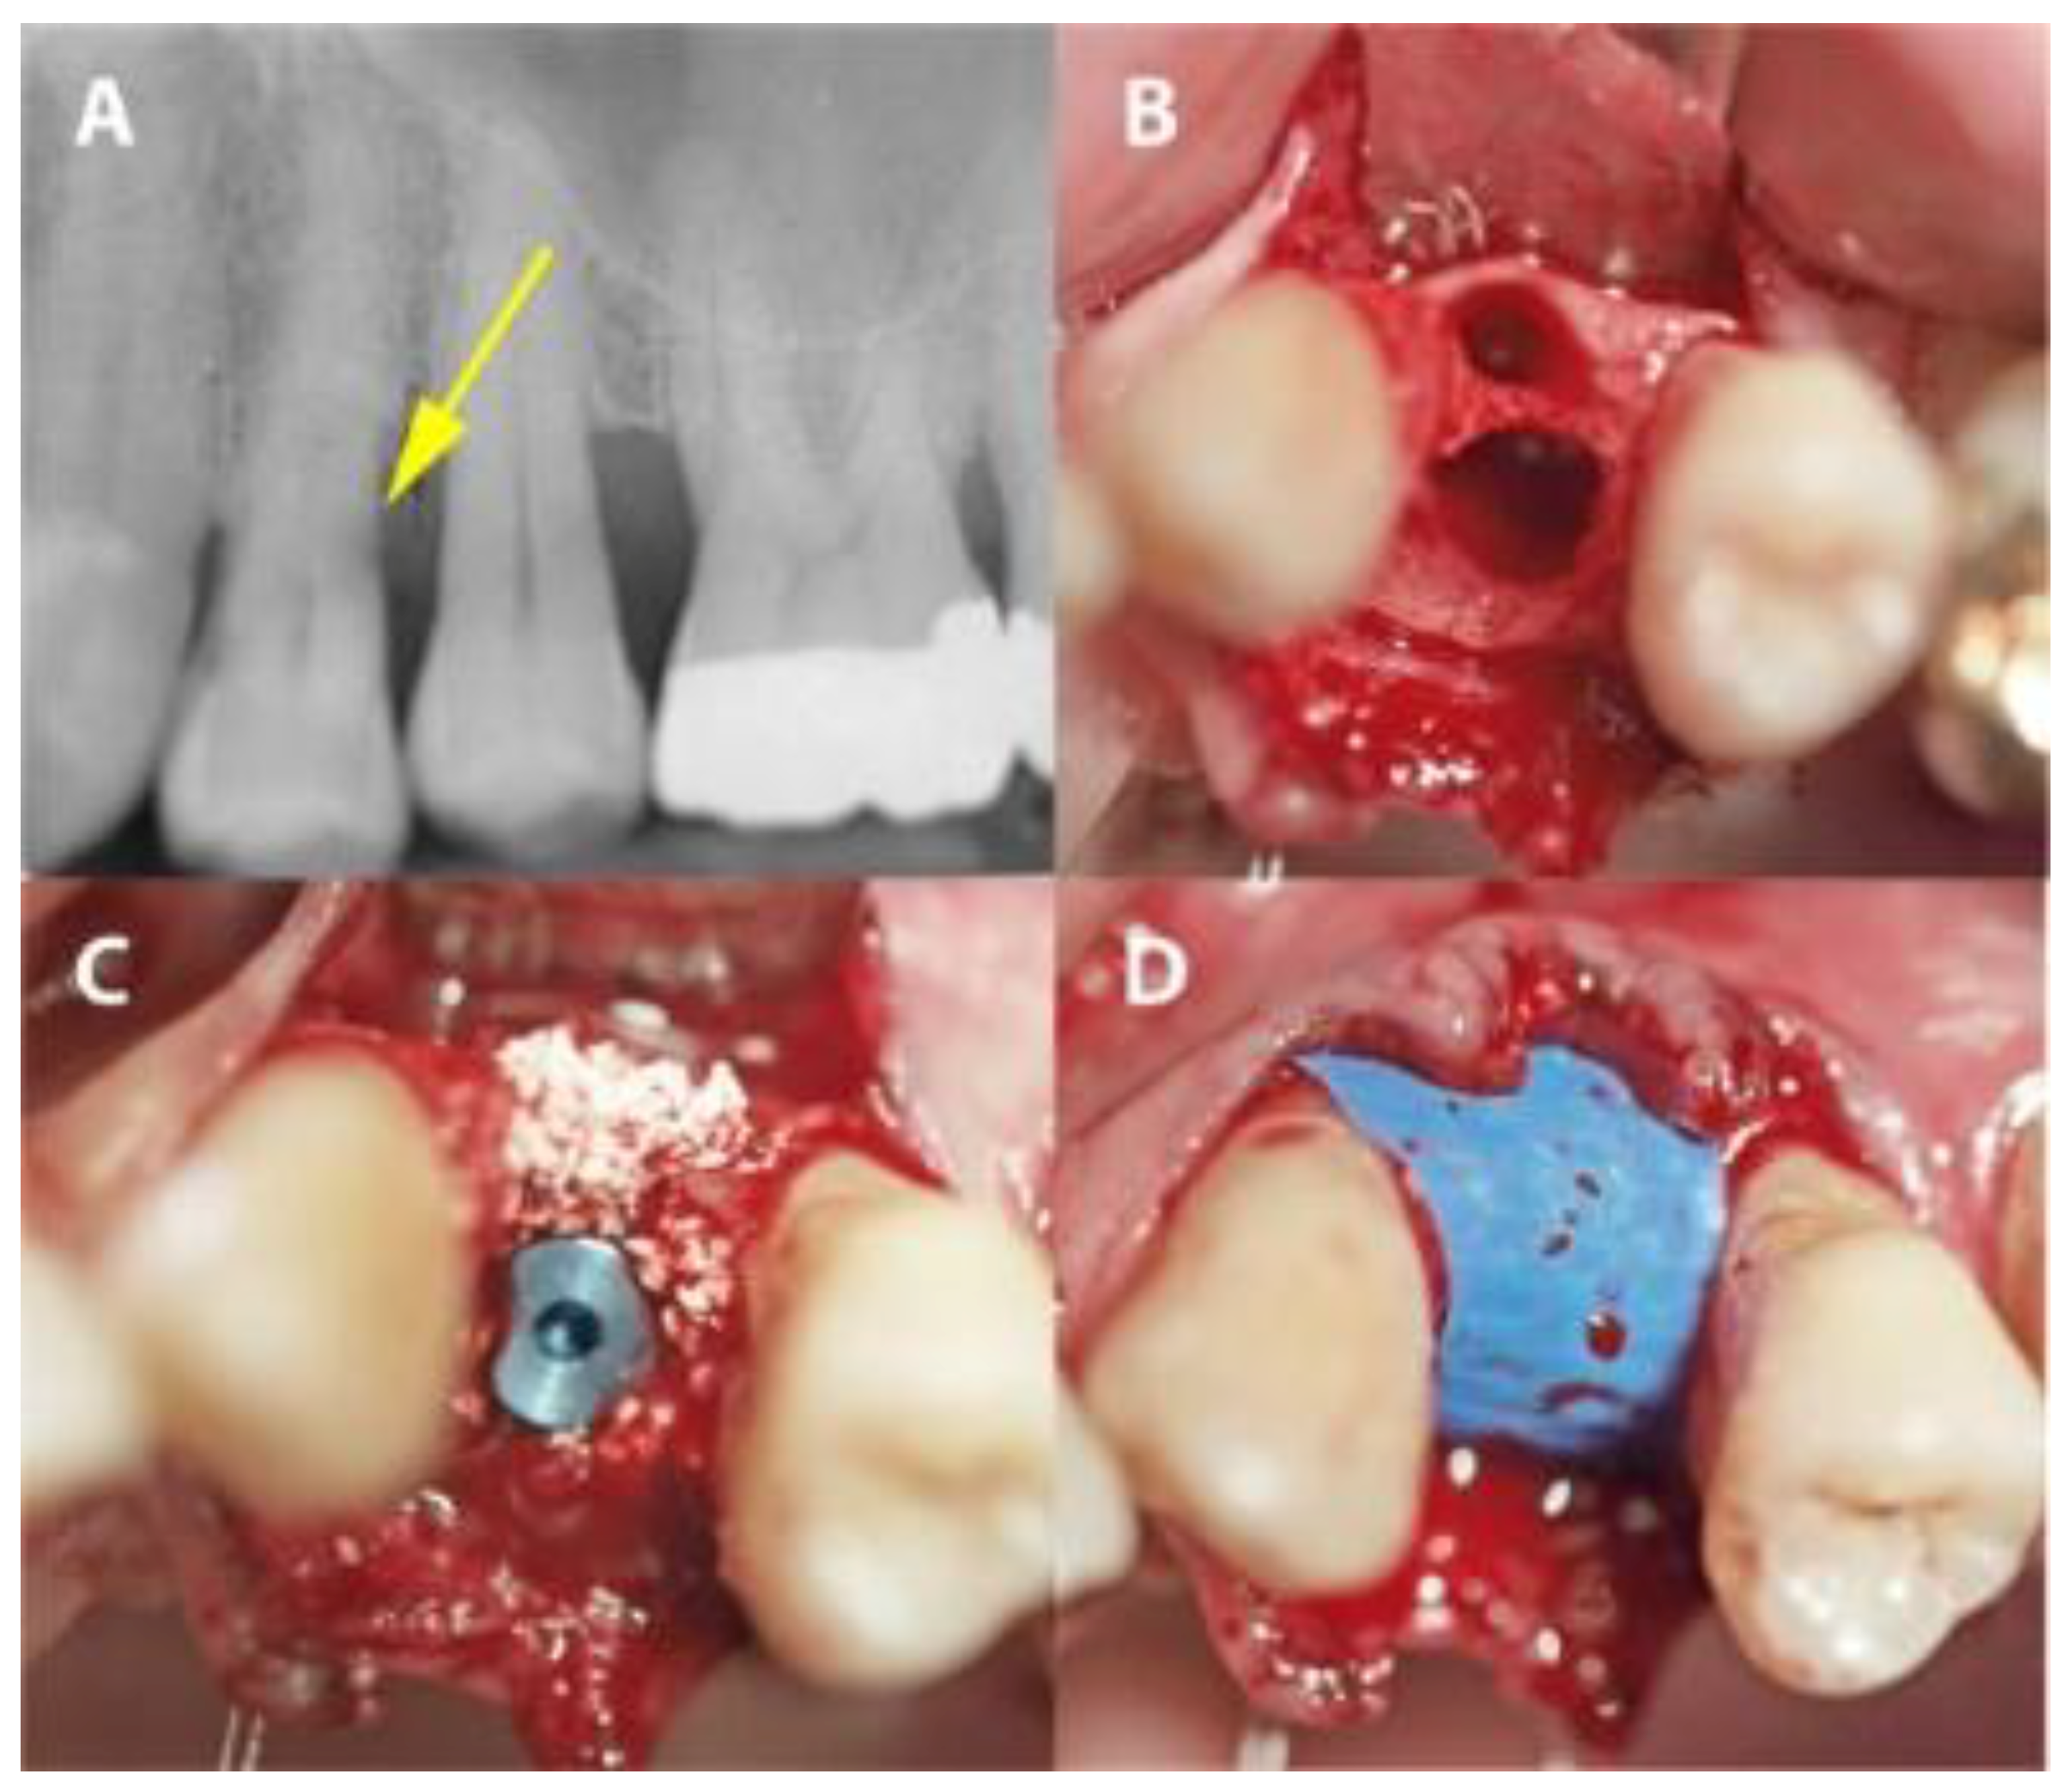

2.2. Surgical Procedure